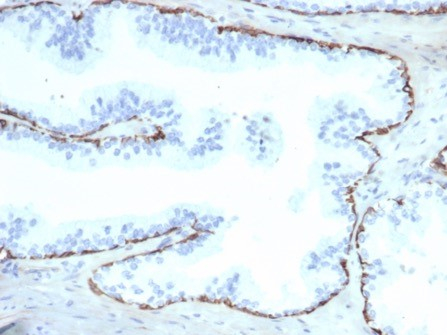

Formalin-fixed, paraffin-embedded human prostate stained with Cytokeratin 14 antibody (KRT14/6987R). HIER: Tris/EDTA, pH9.0, 45min. Secondary: HRP-polymer, 30min. DAB, 5min.